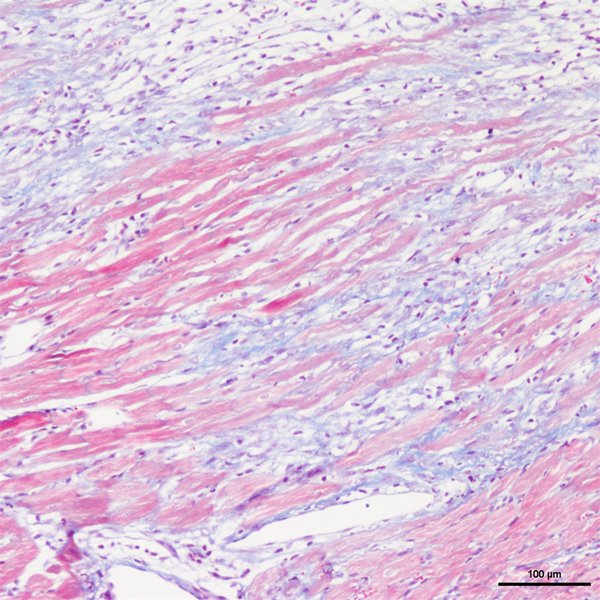

Masson染色

丽春红酸性品红-苯胺蓝染色,是用于检测动物组织中胶原纤维的一种染色方法之一,能够将胶原纤维染成蓝色,肌纤维、和红细胞呈红色,可用于鉴胶原纤维和肌纤维;并显示各种组织胶原纤维含量及纤维化程度。

Masson染色时胶原纤维呈蓝色(被苯胺蓝所染)或绿色(被亮绿所染),肌纤维呈红色(被酸性品红和丽春红所染),这与阴离子染料分子的大小和组织的渗透性有关。如已固定的组织用一系列阴离子水溶性染料先后或混合染色,则可发现红细胞被最小分子的阴离子染料着染,肌纤维与胞质被中等大小的阴离子染料着染,而胶原纤维则被大分子的阴离子染料着染。由此说明了红细胞对阴离子染料的渗透性最小,肌纤维与胞质次之,而胶原纤维具有最大的渗透性。根据组织不同的渗透性能,选择分子大小不同的阴离子染料进行染色,便可把不同组织成分显示出来。

实验结果展示:

masson-心梗>